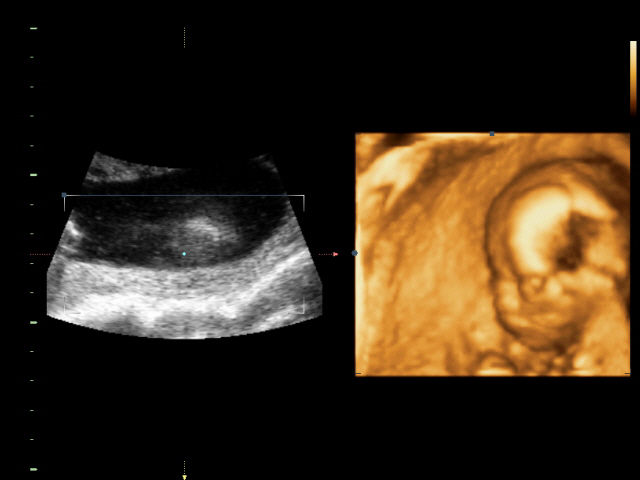

УЗИ, КТГ, доплерСходили всей семьей на 4D УЗИ! Определили нам пол окончательно и бесповоротно! Мальчик! Показали писюн! Так здорово! Я просто поверить не могу! А ведь он мне два раза снился! Настоящий реальный мужчина! Все показатели у нас в норме.